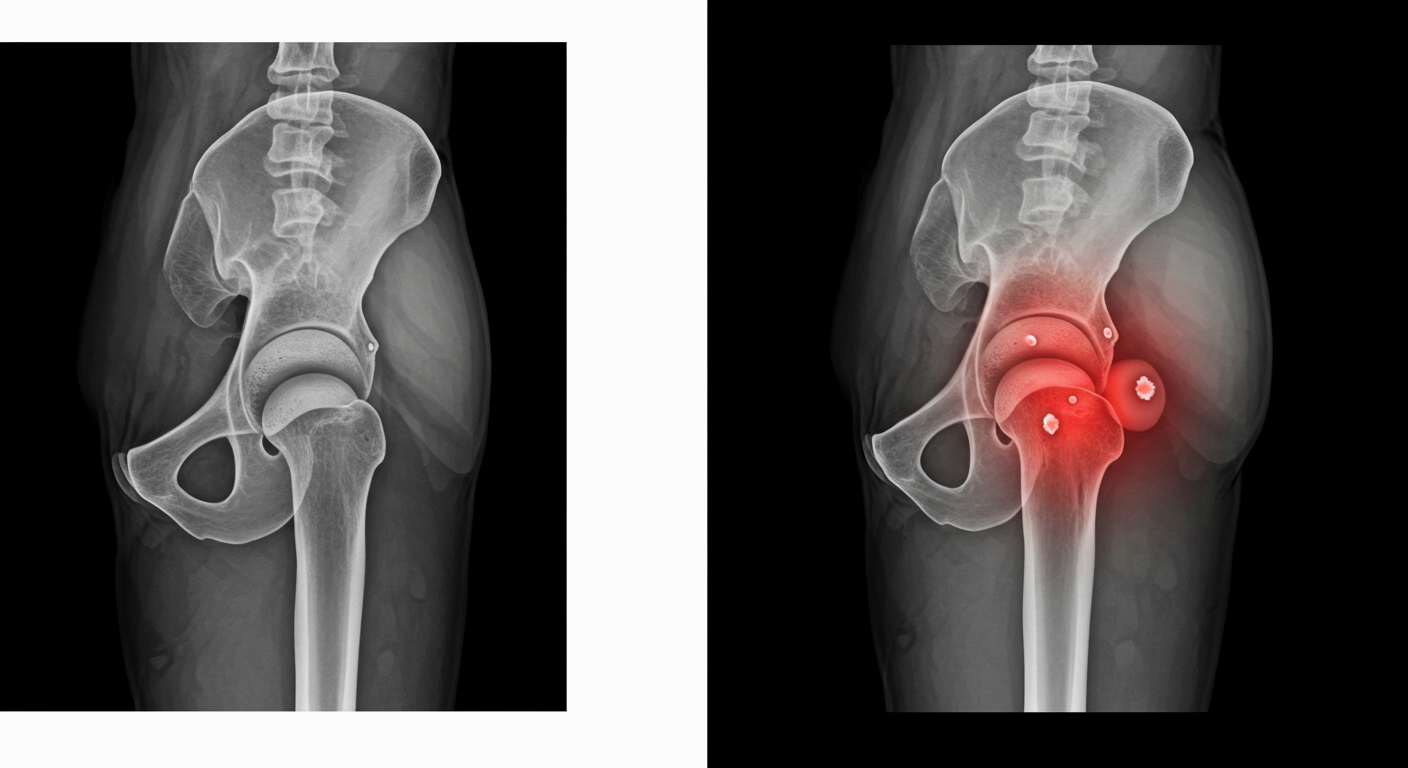

고관절 통증 원인, 왜 아픈 걸까요?

고관절은 골반과 허벅지를 연결하는 관절로, 걷기, 앉기, 뛰기 등 거의 모든 움직임에 관여합니다.

이 중요한 관절에 통증이 생기는 이유는 단순히 ‘나이 때문’만이 아닙니다.

현대인의 생활 습관, 체형, 근육 불균형, 퇴행성 변화 등이 복합적으로 작용해 고관절을 손상시키는 경우가 많습니다.

📌 고관절 충돌 증후군 (FAI)

- 대퇴골두와 비구가 부딪히는 구조적 이상으로 통증 유발

- 주로 젊은 운동선수나 활동량이 많은 사람에게 발생

📌 대퇴골두 무혈성 괴사

- 혈액 공급 부족으로 뼈 조직이 괴사되어 통증 유발

- 음주, 스테로이드 과다 사용 등도 원인이 될 수 있음